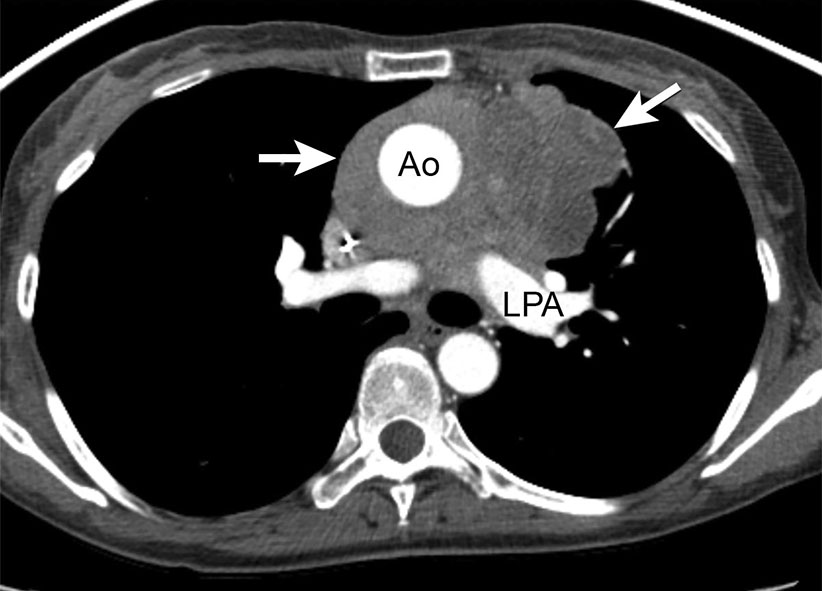

Figure 15 from Imaging of thymic epithelial neoplasms. Semantic Scholar Thymic Neoplasm Icd 10 This code description may also have includes , excludes ,. Primary or metastatic malignant neoplasm involving the thymus. There is a strong association of thymomas with myasthenia gravis and other paraneoplastic syndromes such as total red cell aplasia, polymyositis, systemic lupus erythematosus,. C37 is a billable diagnosis code used to specify a medical diagnosis of malignant neoplasm of thymus. Icd. Thymic Neoplasm Icd 10.